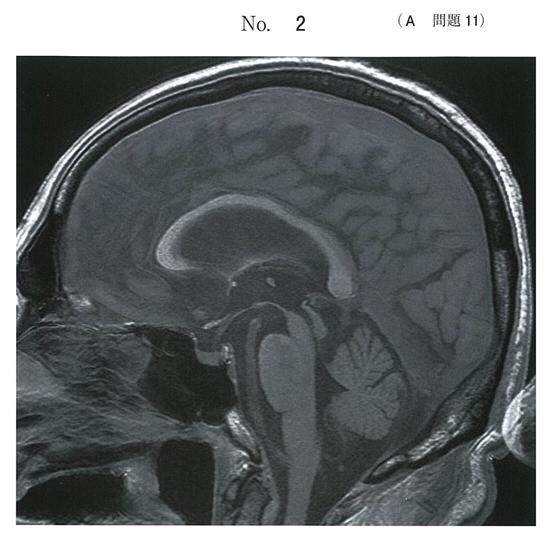

それぞれに、画像上の特徴がありますよね

ただ、Parkinson病と大脳皮質基底核変性症をsagittal で見分けろ、と言われると、果てしなくしんどいですけど…